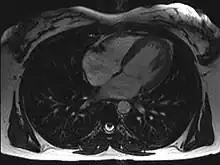

![]() An MRI of a 13 year old female's heart beating. | |

Magnetic resonance imaging visualizes the heart by detecting hydrogen atoms using superconducting magnets, particularly those attached to water and fat molecules.[9] These hydrogen atoms possess a property known as nuclear spin. Although the direction of this spin is usually random, the spin can be aligned using a powerful magnetic field.[9] Faint electromagnetic signals are emitted by these hydrogen atoms when their alignment is temporarily disturbed which can be detected and used to create an image of the heart.[10]

Cardiovascular magnetic resonance (MR) technology is able to measure the size, shape, function, and tissue characteristics of the heart in a single session.[11] It is also commonly used to determine ventricular function and for the evaluation of structural heart disease.[12] It is more reproducible than echocardiography with less inter-observer variability, allowing for more precise reference ranges to better distinguish health from disease.[11] Additionally, MR lacks ionizing radiation and does not have any known long-term effects, making it safe for repeated imaging.[13]

Additional benefits from cardiac MRI include the ability to detect scar within the heart using late gadolinium enhancement, and identify other abnormalities of the heart muscle itself such as infiltration with iron or amyloid protein.[11] Disadvantages of MRI include lengthy protocols and the potential for claustrophobia. Furthermore, an MRI scan cannot be performed in some people who have metallic implants such as some types of pacemakers, defibrillators, although many modern pacemakers are safe for use within an MRI scanner.[14] Other metal structures such as artificial valves and coronary stents are generally not problematic. However, MR is less widely available and may be more difficult for patients to tolerate than other noninvasive modalities, requiring physician monitoring for complex cases.[13]

Recent development in deep learning and convolutional neural network techniques have made it possible to analyze and quantify some aspects of cardiac MRI automatically.[15] The use of cardiac MRI is projected to increase through greater availability of scanners and more widespread knowledge about its clinical application.